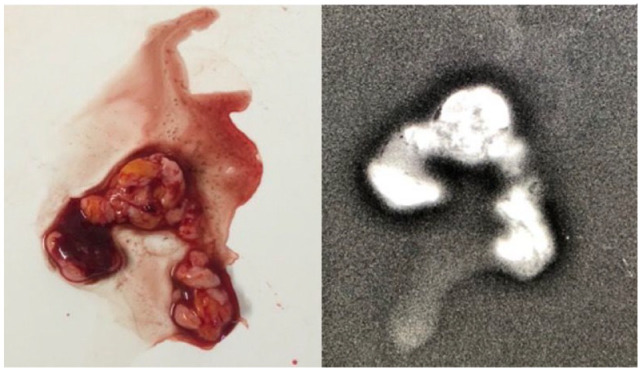

Methods: This was a prospective study conducted between October 1, 2019, and March 31, 2021. Patients with early breast cancer, estrogen and progesterone receptors negative and either Her2 positive or negative, and who were fit to undergo marker placement at the centre of the tumour and to receive third-generation chemotherapy (4 cycles of 3 weekly doxorubicin and cyclophosphamide followed by 4 cycles of 3 weekly docetaxel) were included in the study. Following the enrolment, a tissue marker was placed at the centre of the tumour and appropriate chemotherapy was started. Patients who achieved clinical complete response were subjected to ultrasound-guided vacuum-assisted biopsy (VAB) from the tumour bed before surgery. Pathology results of the VAB and resected specimen were then compared. Descriptive statistics were used in the study.

Results: Eighteen patients were enrolled in the study, with a mean age of 43.6 ± 9.8 years. However, only 10 were eligible for VAB procedure, and sensitivity and specificity were calculated based on the results of these 10 patients only. Vacuum-assisted biopsy showed sensitivity of 50% and specificity of 100% in identifying pCR. Combination of mammography, ultrasonography, and VAB showed sensitivity of 77.8% and specificity of 66.7% in identifying pCR.

Conclusion: Vacuum-assisted biopsy of tumour bed may not be sensitive enough to eliminate surgery even in patients who have had exceptional response to neo-adjuvant chemotherapy.